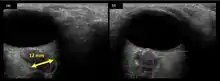

The fourth case of visual changes on orbit was significant for a history of transsphenoidal hypophysectomy for macroadenoma where postoperative imaging showed no residual or recurrent disease. Approximately 2 months into the ISS mission, the astronaut noticed a progressive decrease in near-visual acuity in his right eye and a scotoma in his right temporal field of vision.[5]

Figure 5: On-orbit ultrasound of posterior orbit of the fourth case of visual changes from long-duration spaceflight. In-flight ultrasound image of the right eye showing posterior globe flattening and a raised optic disc consistent with optic-disc edema and raised ICP.

Figure 6: On-orbit ultrasound of optic nerves of the fourth case of visual changes from long-duration spaceflight. In-flight ultrasound shows proximal kinking and increased optic nerve sheath diameter (ONSD) of approximately 12 mm that is consistent with raised ICPs. Optic nerve shown in purple and the ONSD in green.